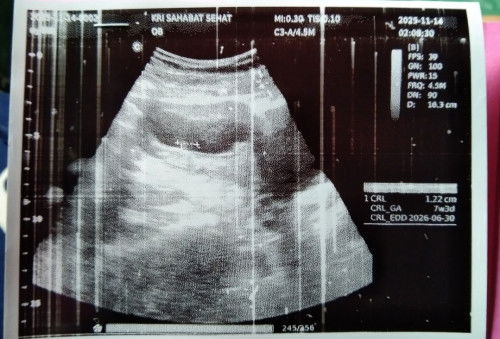

Akhirnya usg pertama kalinya. Alhamdulillah hamil didalam rahim. Tapi usia kemailannya 6w kalo berdasarkan hpht baru 4w

kalau kayak gini gimana bunda". katanya kantung nya masih 0,61cm. dan CRL nya 1,22cm apakah beneran hamil soalnya waktu diterangin dokter nya agak ngang ngong bund🥲